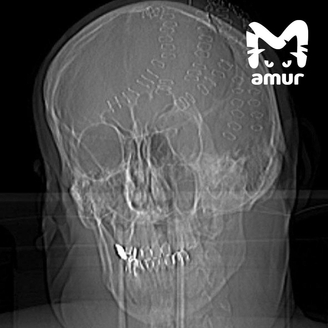

Некоторое время назад в больницу Владивостока доставили мужчину с острова Попова. У 50-летнего гражданина была разбита голова. Снимок показал, что череп проломлен в нескольких местах. Также выяснилось, что у пациента началось кровоизлияние в мозг. Сам он впал в шоковое состояние.

Врачи провели долгую и сложную операцию, в ходе которой смогли собрать череп буквально по кусочкам. Некоторые фрагменты пришлось убрать вовсе. Состояние пациента стабильное.

Фото: Telegram / Amur Mash